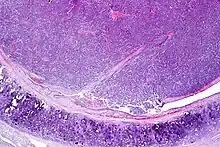

| Atypical pulmonary carcinoid. H&E stain. | |

Atypical carcinoid tumors have increased mitotic activity (2-10 per 10 HPF), nuclear pleomorphism or foci of necrosis.